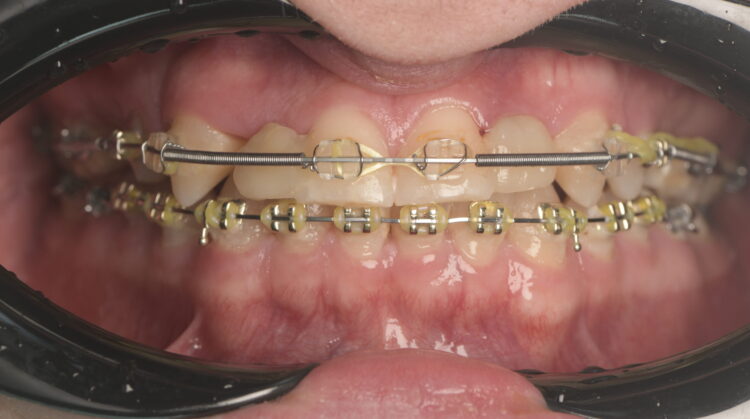

The patient visited the orthodontist for the first phase of treatment. Before the appliance was removed, I confirmed that the desired tooth positions had been achieved to ensure adequate spaces for implant placement.

A CBCT scan was taken using a Morita X800. This dataset was imported into the planning software, where it was merged with the STLs of the anatomically correct diagnostic digital wax-up and modules.  With the anatomically correct diagnostic wax-up, there was no ambiguity regarding planning the implant position, angle and depth with precision. I like to plan these types of cases myself, but it is possible to outsource the planning stage for clinicians who are new to the process and looking to increase their workflow efficiency. For this case, I wanted to build up the gingival thickness in order to improve the papillae around the implant sites. The surgical plan, therefore, included soft tissue grafting.

On the day of surgery, a split-thickness envelope flap was raised. Two CONELOG® Progressive-Line implants were placed through the surgical guide in the pre-determined lateral incisor positions. Soft tissue augmentation was performed simultaneously with the implant placement, and the site was sutured and closed without tension. The implants were immediately loaded using provisional crowns that were pre-fabricated in the lab.